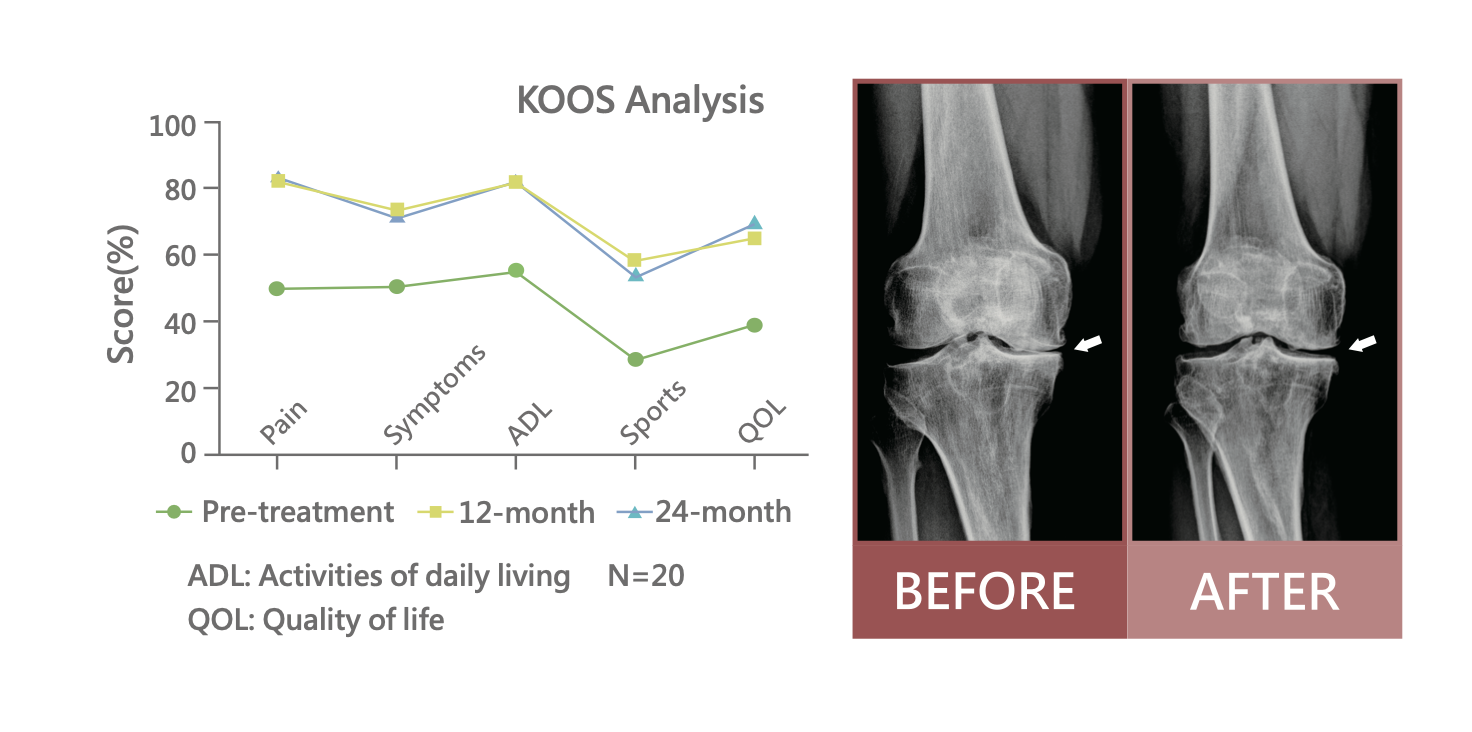

退化性關節炎臨床成果

臨床成果頁顯示,AI Cells 可有效改善退化性關節炎患者的疼痛,並提升運動功能。圖中以 KOOS Analysis 呈現疼痛、症狀、日常活動、運動能力與生活品質等指標,於追蹤 12 個月與 24 個月時皆可見改善趨勢。

此外,關節腔內注射 AI Cells 治療後,也可見軟骨下骨水腫症狀減輕的影像案例,顯示其在退化性關節炎臨床應用上具有參考價值。